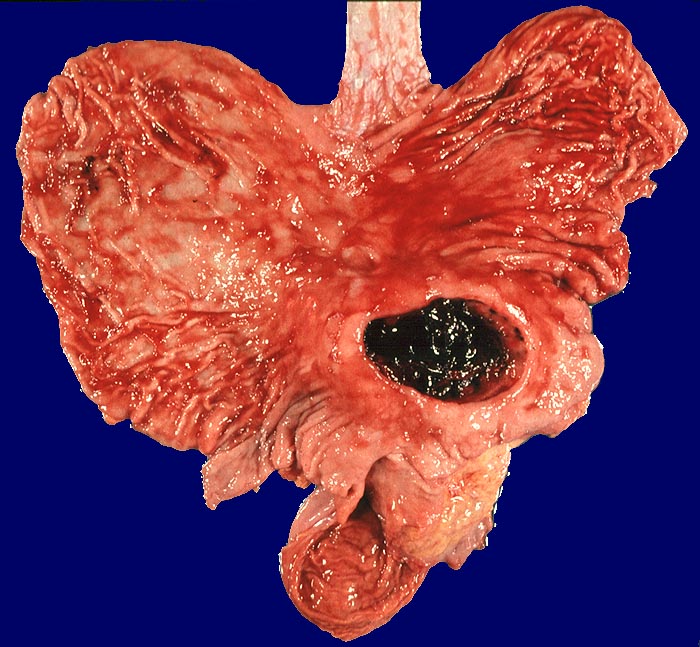

Unter einem Ulkus des Magens oder des Duodenums versteht man einen von der Schleimhaut ausgehenden Substanzdefekt, der die Lamina muscularis mucosae überschreitet. Endoskopisch

wird die Diagnose eines Ulkus bei Schleimhautläsionen

von mehr als 5 mm Durchmesser gestellt.

Das akute Ulkus ist rund, oval oder seltener polyzyklisch begrenzt und liegt meist im Schleimhautniveau. Das chronische Ulkus ist häufig kreisrund und im Längsschnitt trichter- oder treppenförmig. Die Schleimhautränder können lippenförmig über den Ulkusgrund hinausragen. Palpatorisch ist das chronische Ulkus aufgrund der narbigen Fibrose induriert. Die Schleimhautfalten laufen sternförmig auf das Ulkuszentrum zu. Das chronische Ulkus tritt zu 10%, das akute zu 25% multipel auf. Mikroskopisch zeigt das chronische Ulkus eine typische Schichtung (s. Bilder). Die Gefässe im Ulkusgrund zeigen eine starke Intimaproliferation mit teilweiser oder vollständiger Obliteration der Gefässlichtung. Morphologische Veränderungen in der übrigen Magenschleimhaut geben einen Hinweis auf die Ätiologie des Ulkus (Typ B oder C Gastritis).